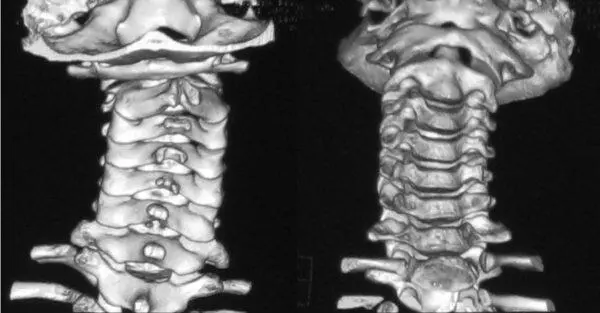

Рис. 6.17.3D КТ пациентки 12 лет с застарелым атлантоаксиальным блокированием. CI смещен влево и кпереди

На функциональных КТ движения в CI–CII отсутствовали при фиксированном латеральном подвывихе атланта (рис. 6.17). Голова была в типичном положении «верхней» кривошеи – со смещением вперед и в сторону (рис. 6.18).